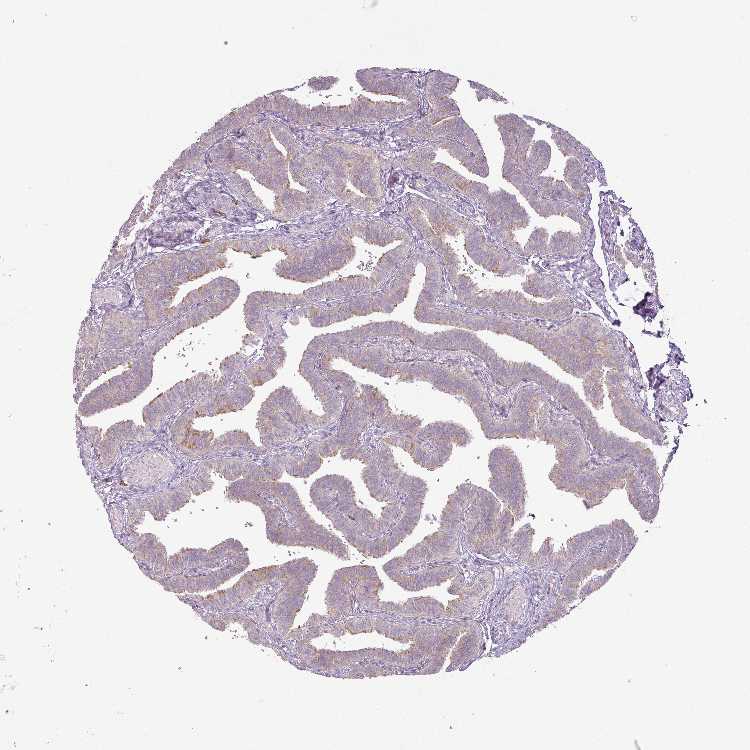

TISSUE PRIMARY DATA FALLOPIAN TUBE Show tissue menu

FALLOPIAN TUBE - Antibody stainingi

Antibody staining in the annotated cell types in the current human tissue is reported as not detected, low, medium, or high, based on conventional immunohistochemistry profiling in selected tissues. This score is based on the combination of the staining intensity and fraction of stained cells.

Each image is clickable and will lead to virtual microscopy that enables deeper exploration of all samples and also displays staining intensity scores, fraction scores and subcellular localization as well as patient and tissue information for each sample.

Antibody HPA049108Antibody CAB001450

Ciliated cells (cell body) -Medium

Ciliated cells (cilia axoneme) -Not detected

Ciliated cells (ciliary rootlets) -Not detected

Ciliated cells (tip of cilia) -Not detected

Glandular cells Medium-

Non-ciliated cells -Not detected